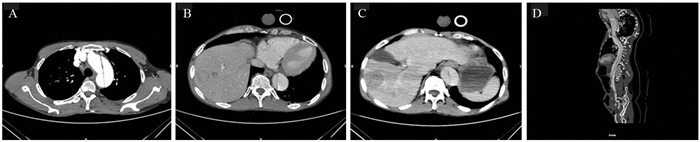

1 病例资料患者,男,63岁。2018年8月,因“上腹部疼痛4月,加重伴剑突下疼痛12 h以上”入院。家属诉患者入院前4月因右上腹疼痛,于当地医院检查,诊断“肝癌肝内转移”,并给予“阿帕替尼片、恩替卡韦片、肝苏颗粒、甘草酸二铵肠溶胶囊”口服。定期复查增强CT。1周前,因右上腹胀痛于门诊就诊,腹部增强CT示肿瘤稳定,见图 1。给予盐酸曲马多缓释胶囊100 mg每12 h口服一粒,疼痛控制可。12 h前,无明显诱因下出现剑突下疼痛,呈持续性撕裂样疼痛,先后口服2粒盐酸曲马多缓释胶囊不缓解,伴有头晕,无声嘶、胸痛、胸闷,无恶心、呕吐,无血尿等。否认高血压、冠心病、先天性心脏病、胸部外伤、梅毒等病史。查体:体温36.6℃,脉搏71次/分,呼吸20次/分,血压:169/110 mmHg。神志清楚,急性痛苦面容。言清语利,无口角歪斜、复视、视力减退等,四肢肌力感觉正常,颈部未闻及血管杂音,心肺(-)。无声嘶、声哑; 上腹部疼痛,剑突下压痛,未触及异常搏动性肿块; 肝脾肋下未触及,肠鸣音4次/分; 左上腹可闻及血管杂音,余中下腹部未闻及血管杂音。双上肢桡动脉、足背动脉、胫后动脉、胫前动脉搏动有力对称。疼痛评估数字分级(numberical rating scale, NRS)评分:8分。胸部CT平扫,见图 2。升主动脉-胸主动脉增粗呈双腔改变,可见内膜移位; 考虑主动脉夹层或壁内血肿,建议CT血管造影(CT angiography, CTA)检查。心电图:左室高电压; 完全性右束支阻滞; 左前分支阻滞; T波改变。血常规、肝肾功能、电解质、输血前检查未见异常。弥散性血管内凝血(disseminated intravascular coagulation, DIC):D-二聚体11.23 μg/ml; 纤维蛋白原降解产物20.80 μg/ml。心肌损伤标志物:高敏肌钙蛋白T 0.01 μg/L; 肌红蛋白47.1 μg/L; N-末端脑利钠肽前体(Nt-BNP)285.3 ng/L; 肌酸激酶同工酶2.55 μg/L。入院诊断:(1)主动脉夹层; (2)高血压; (3)肝癌肝内转移。给予止痛、控制血压,转往血管外科CTA明确诊断,见图 3,患者及家属拒绝手术,保守治疗后要求出院。

| A: thoracic plain CT shows aortic arch level, visible arterial intimal displacement; B: T8 level, thoracic aorta coarsening shewed double lumen changes, visible intimal displacement 图 2 入院胸部平扫提示主动脉-胸主动脉增粗呈双腔改变,可见内膜移位 Figure 2 On plain chest scan, the coarsening of aorta and thoracic aorta showed double lumen changes, and the displacement of intima could be seen |

| A: intimal patches in the horizontal aortic arch; B, C: abdominal aortic horizontal artery intima patches, non-uniform enhancement patches in the right lobe of liver, multiple nodular mild enhancement patches in the liver parenchyma; D: intimal patches could be seen from the horizontal aortic arch to the right common iliac artery 图 3 患者主动脉CT血管造影 Figure 3 Aorta CT angiography of the patient |